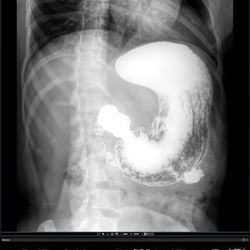

Histerosalpingografía

Aplicación en angiografía periférica  y sustracción digital.